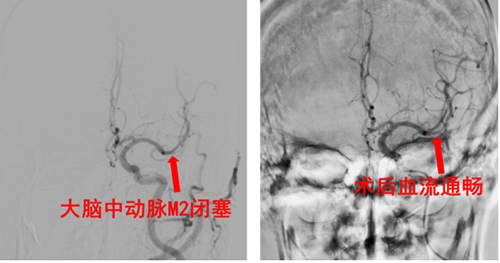

病例3(技术攻坚典范)——“生命通道”的极限修复:一位55岁男性,因突发左侧偏瘫、意识不清由120紧急送医。神经内科立即予以静脉溶栓,同时脑卒中一站式检查发现其右侧颈内动脉颅外段已完全闭塞,大脑面临严重缺血。神经外科介入团队在手术中遭遇了巨大挑战:患者病因并非普通血栓,而是颈动脉血管壁撕裂(夹层) 造成的闭塞,同时脱落的血栓还堵塞了大脑中动脉M2段;更棘手的是,通往病变的血管路径存在360°极度迂曲,器械通过异常困难。面对这一复杂险情,团队凭借高超的技术与丰富的经验,迎难而上。不仅将远端血栓悉数取出,更成功在颈动脉夹层部位精准植入支架,封堵破口,使夹层完美愈合,血流通畅恢复。术后患者恢复显著,意识完全清醒,并可自主下地行走。此例手术的成功,是我院在卒中介入领域实现的一项重大技术突破。

病例4——远端血管的精细开通:一位61岁男性,因突发右侧偏瘫伴失语4小时来院。检查提示为左侧大脑中动脉M2段起始部闭塞。尽管闭塞血管更细、位置更深,团队依然凭借精湛技艺成功施行取栓,实现血流通畅。